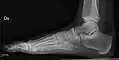

- Foot / Toes - Dorsoplantar, Oblique and Lateral.[19]

Normal right foot by dorsoplantar projection

Oblique projection

Lateral projection